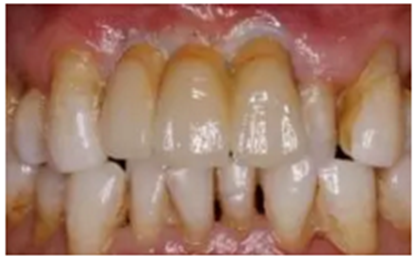

(6)最終修復(fù)體戴入

(7)修復(fù)6個月后復(fù)查

結(jié)合PRF的位點保存術(shù)后牙槽嵴輪廓豐滿,CBCT示骨量充足,數(shù)字化種植外科導(dǎo)板輔助下植體植入三維位置精確,種植體骨結(jié)合良好,數(shù)字化口掃系統(tǒng)數(shù)據(jù)采集高效、精確,臨時修復(fù)體戴入,軟組織成形,最終修復(fù)體戴入后穩(wěn)定、密合,牙齦軟組織色澤形態(tài)正常,美學(xué)效果良好。